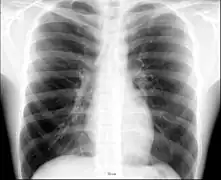

Placa posteroanterior de tórax en el sujeto normal.